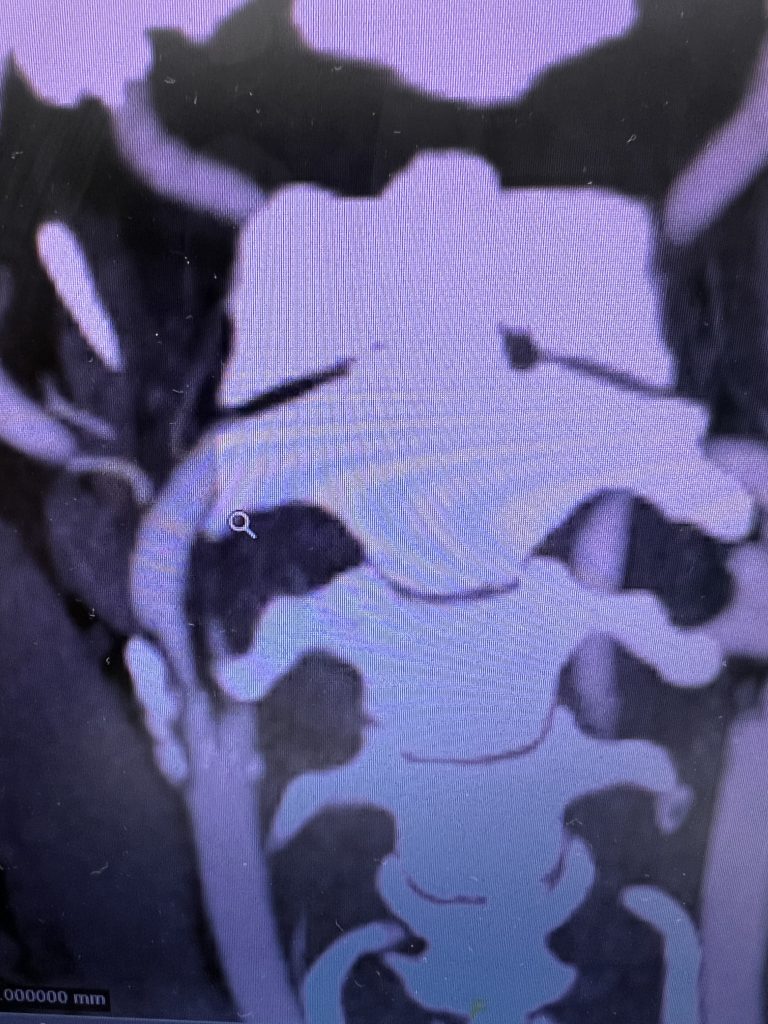

Fig. 1 – Pre-operative imaging using a diffusion-weighted image sequence, shows multiple areas of most likely embolic stroke in the right frontal white matter.

MRI imaging using the diffusion-weighted image sequence, which is highly sensitive for acute stroke showed multiple areas of most likely embolic stroke in the right frontal white matter (Figure 1) as well as the right corona radiata (Figure 2).